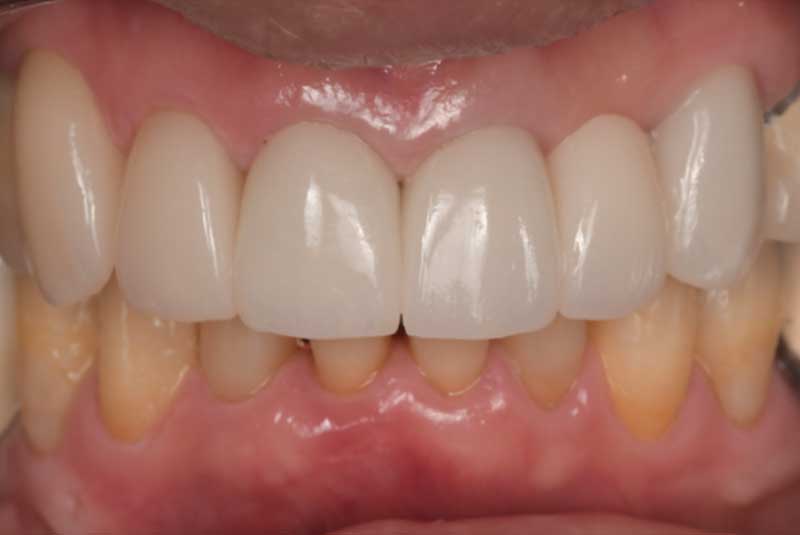

All on 6: Monolithic Zirconia Full arch prosthesis & Crown Lengthening, Veneers, Crowns, Onlays